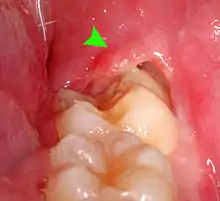

Pericoronitis

Pericoronitis is inflammation of the soft tissues surrounding the crown of a partially erupted tooth.[25] The lower wisdom tooth is the last tooth to erupt into the mouth, and is, therefore, more frequently impacted, or stuck, against the other teeth. This leaves the tooth partially erupted into the mouth, and there frequently is a flap of gum (an operculum), overlying the tooth. Bacteria and food debris accumulate beneath the operculum, which is an area that is difficult to keep clean because it is hidden and far back in the mouth. The opposing upper wisdom tooth also tends to have sharp cusps and over-erupt because it has no opposing tooth to bite into, and instead traumatizes the operculum further. Periodontitis and dental caries may develop on either the third or second molars, and chronic inflammation develops in the soft tissues. Chronic pericoronitis may not cause any pain, but an acute pericoronitis episode is often associated with pericoronal abscess formation. Typical signs and symptoms of a pericoronal abscess include severe, throbbing pain, which may radiate to adjacent areas in the head and neck,[21][26]: 122 redness, swelling and tenderness of the gum over the tooth.[27]: 220–222 There may be trismus (difficulty opening the mouth),[27]: 220–222 facial swelling, and rubor (flushing) of the cheek that overlies the angle of the jaw.[21][26]: 122 Persons typically develop pericoronitis in their late teens and early 20s,[28]: 6 as this is the age that the wisdom teeth are erupting. Treatment for acute conditions includes cleaning the area under the operculum with an antiseptic solution, painkillers, and antibiotics if indicated. After the acute episode has been controlled, the definitive treatment is usually by tooth extraction or, less commonly, the soft tissue is removed (operculectomy). If the tooth is kept, good oral hygiene is required to keep the area free of debris to prevent recurrence of the infection.[21]: 440–441